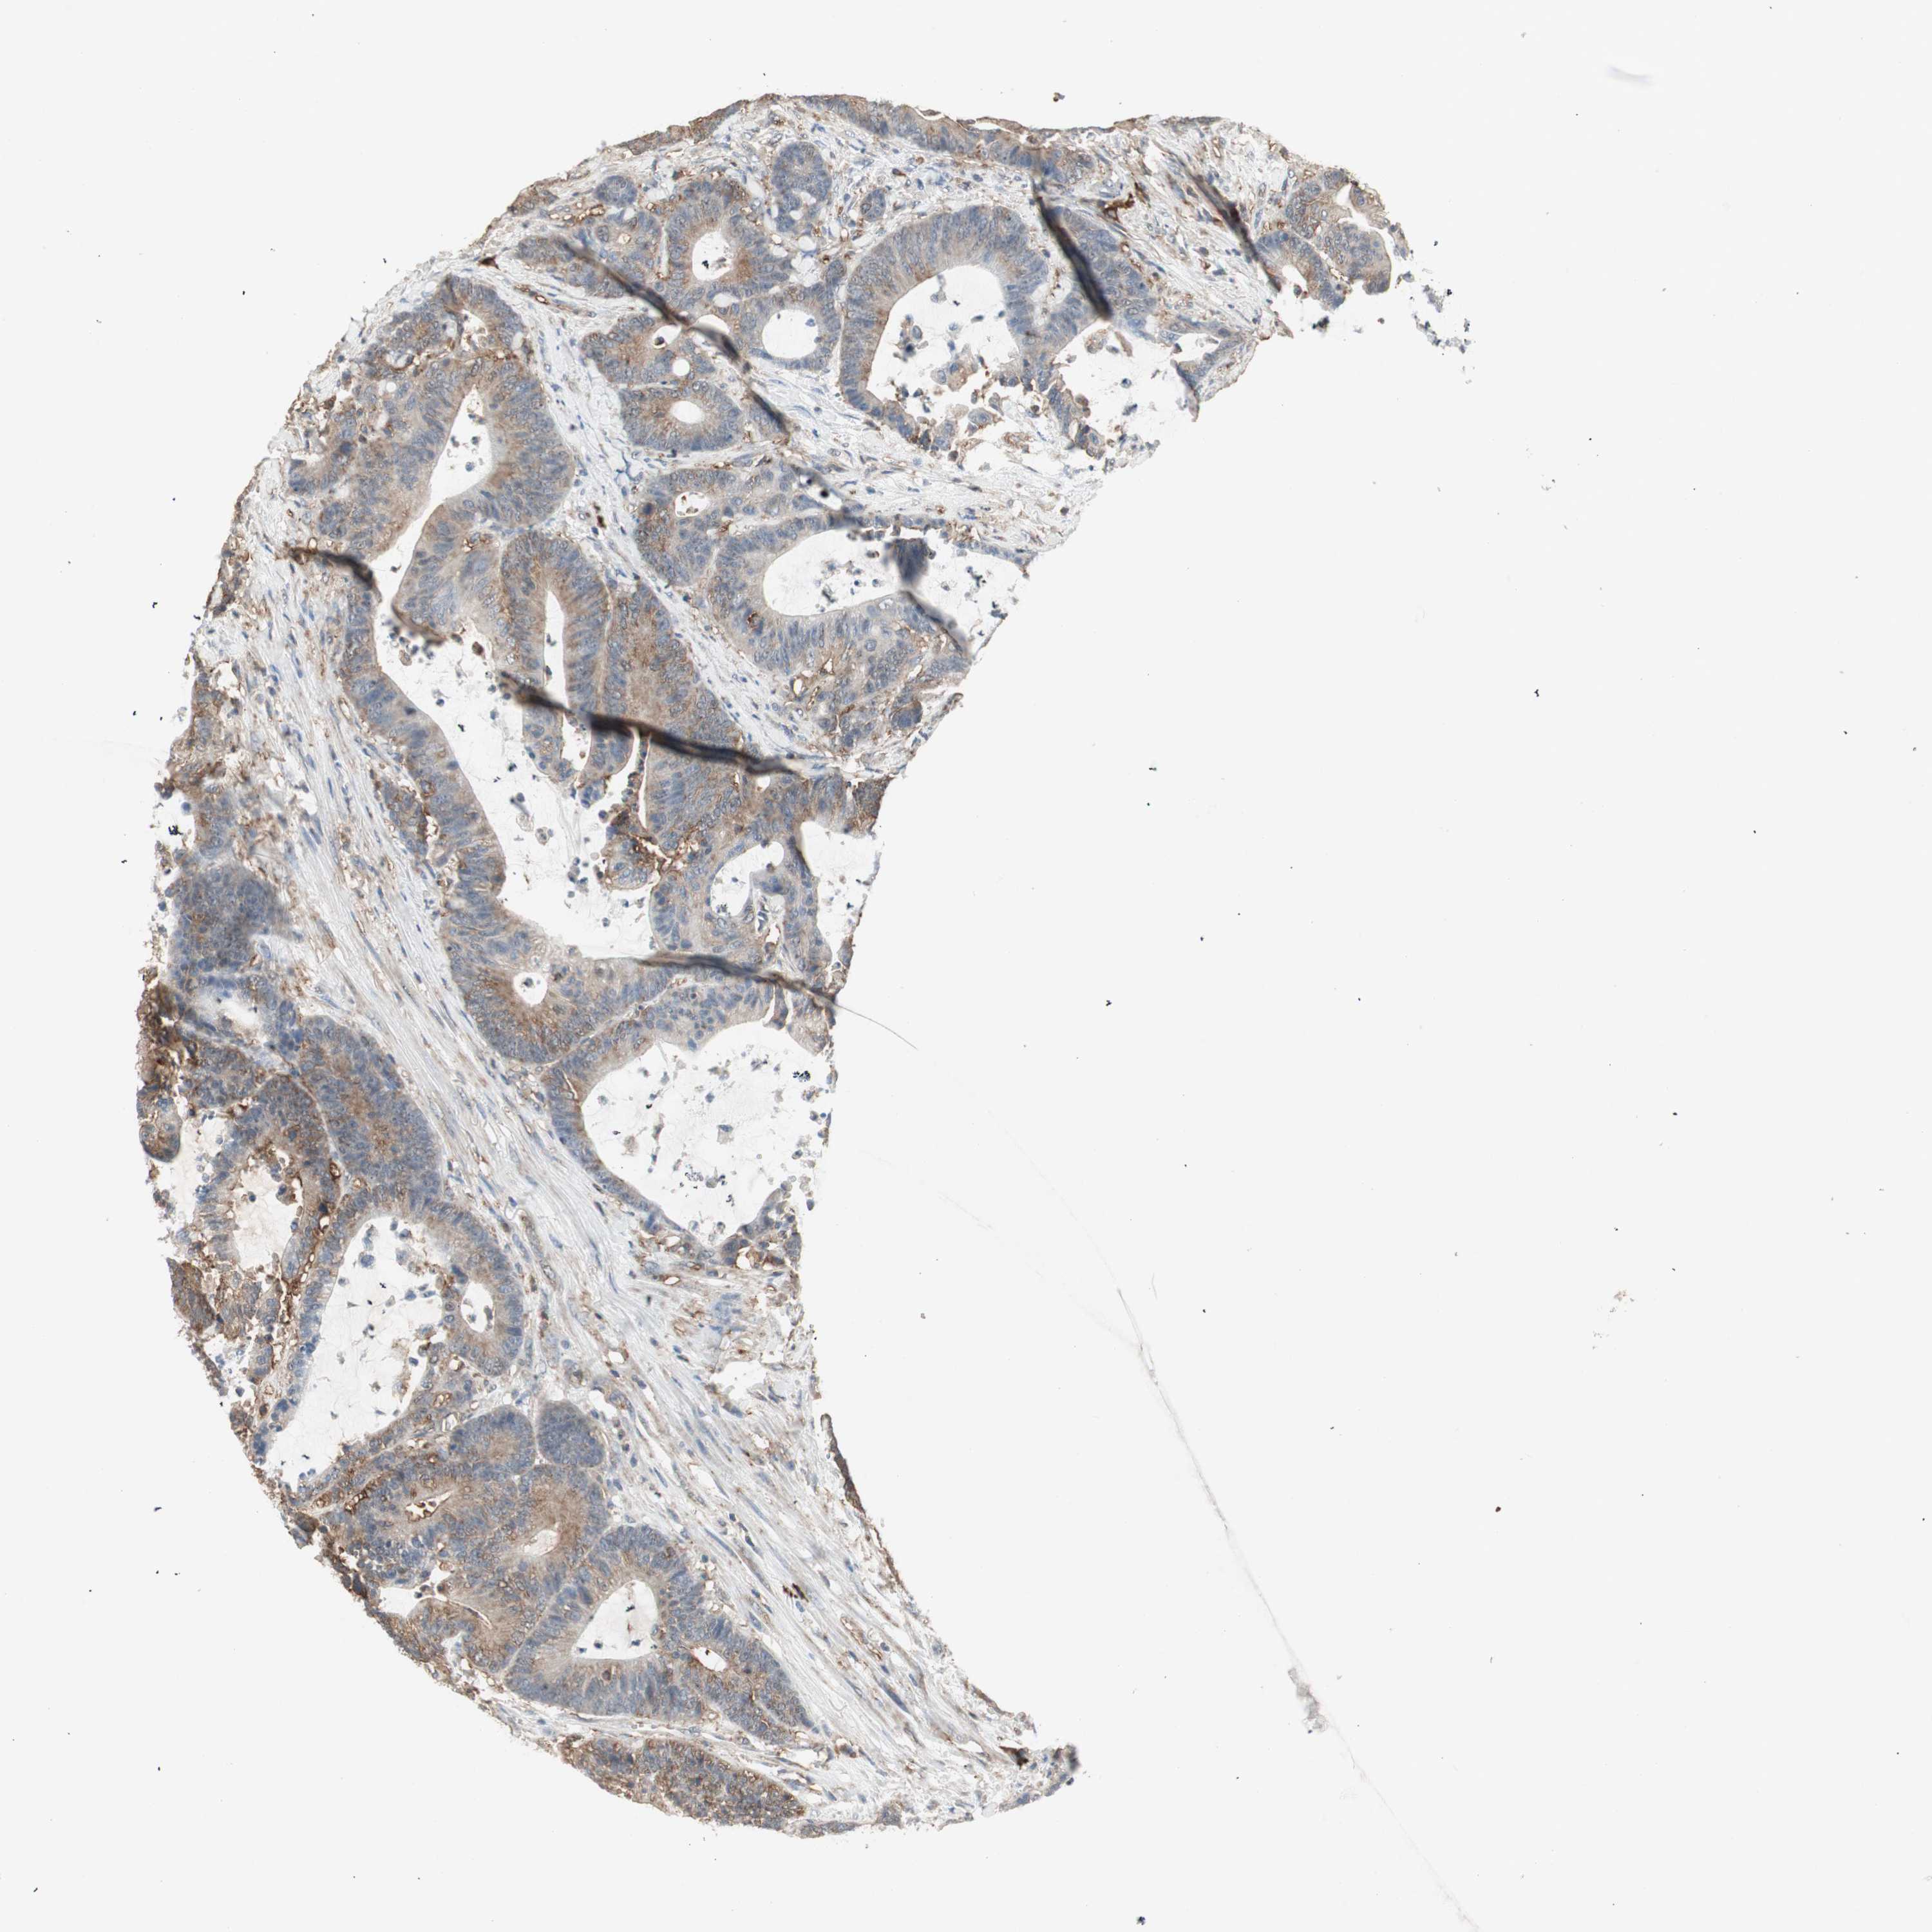

COLON ADENOCARCINOMA (VALIDATION) - Interactive survival scatter ploti

The Survival Scatter plot shows the clinical status (i.e. dead or alive) for all individuals in the patient cohort, based on the same data that underlies the corresponding Kaplan-Meier plots. Patients that are alive at last time for follow-up are shown in blue and patients who have died during the study are shown in red.

The x-axis shows the expression levels (FPKM) of the investigated gene in the tumor tissue at the time of diagnosis. The y-axis shows the follow-up time after diagnosis (years). Both axes are complimented with kernel density curves demonstrating the data density over the axes. The top density plot shows the expression levels (FPKM) distribution among dead (red) and alive patients (blue). The right density plot shows the data density of the survived years of dead patients with high and low expression levels respectively, stratified using the cutoff indicated by the vertical dashed line through the Survival Scatter plot. This cutoff is automatically defined based on the FPKM cutoff that minimizes the p-score. The cutoff can be changed by dragging the vertical line or by entering a cutoff value in the square labeled "Current cut-off".

Under the Survival Scatter plot the p-score landscape (black curve; left axis) is shown together with dead median separation (red curve; right axis). Dead median separation is the difference in median mRNA expression between patients who have died with high and low expression, respectively. It is calculated as follows: median FPKM expression of dead patients with high expression - median FPKM expression of dead patients with low expression. This is intended to aid the user in visually exploring custom cutoffs and the associated p-scores and dead median separation.

Individual patient data is displayed and can be filtered by clicking on one or more of the category buttons on the top of the page. Categories describing expression level and patient information include: high, low, alive, dead, female, male and tumor stages. The scale of the x-axis can be toggled between linear and log-scale by clicking on the "x log" button. Mouse-over function shows TCGA ID, patient information and mRNA expression (FPKM) for each patient.

& Survival analysisi

Kaplan-Meier plots summarize results from analysis of correlation between mRNA expression level and patient survival. Patients were divided based on level of expression into one of the two groups "low" (under cut off) or "high" (over cut off). X-axis shows time for survival (years) and y-axis shows the probability of survival, where 1.0 corresponds to 100 percent.

MMP3 is not prognostic in Colon Adenocarcinoma (validation)

Best expression cut offi

Based on the FPKM value of each gene, patients were classified into two groups and association between prognosis (survival) and gene expression (FPKM) was examined. The best expression cut-off refers the FPKM value that yields maximal difference with regard to survival between the two groups at the lowest log-rank P-value. Best expression cut-off was selected based on survival analysis .

When clicking on this number, the vertical dashed line indicating cut-off, the interactive survival plot, and the Kaplan-Meier curve will be adjusted to show results based on the best expression cut-off.

: 54.99

P scorei

Log-rank P value for Kaplan-Meier plot showing results from analysis of correlation between mRNA expression level and patient survival.

N/A

5-year survival highi

5-year survival for patients with higher expression than the expression cutoff.

For melanoma and glioma, 3-year survival is shown.

5-year survival lowi

5-year survival for patients with lower expression than the expression cutoff.

TCGA RNA samplesi

RNA-seq data is reported as average FPKM (number Fragments Per Kilobase of exon per Million reads), generated by the The Cancer Genome Atlas (TCGA) .

Normal distribution across the dataset is visualized with box plots, shown as median and 25th and 75th percentiles. Points are displayed as outliers if they are above or below 1.5 times the interquartile range. FPKM values of the individual samples are presented next to the box plot.

Average pTPM 140.9

Number of samples 486